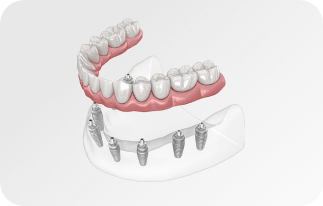

Установка

за 1 день